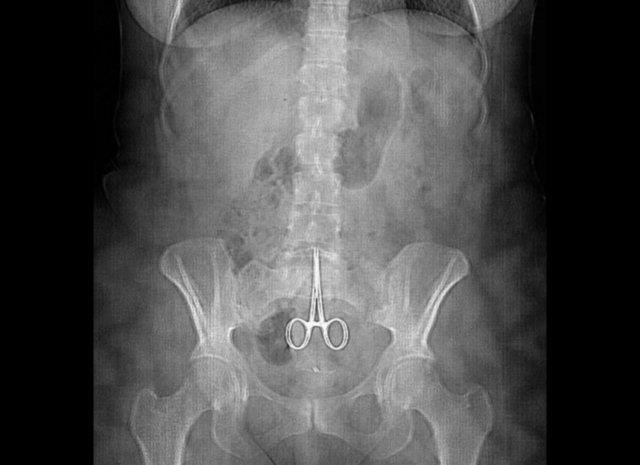

Avusturyalı kadın ameliyat sonrası içinde unutulan makasla 18 ay yaşadı.

Ameliyatının ardından acı çekmeye başlayan Fransız kadının da röntgenlerinden içinde makas unutulduğu ortaya çıktı.

Makası midesinde unuttular.